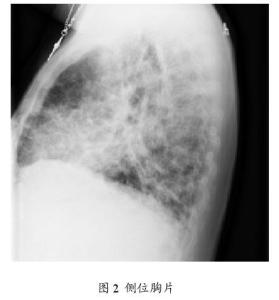

۞ 免疫缺陷性肺炎的检查